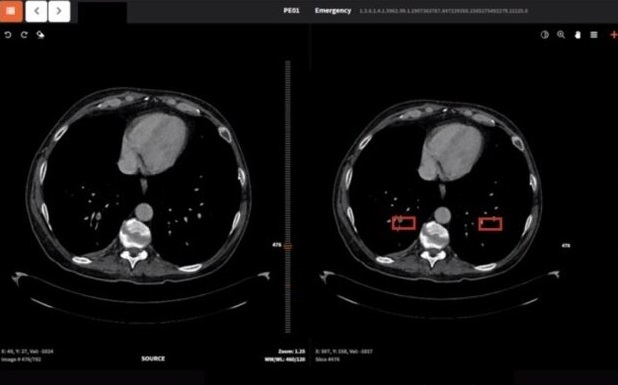

سامانه تشخیص پنومونی کووید ۱۹ با استفاده از نوآوری در پیش پردازش تصاویر سی تی اسکن قفسه سینه و الگوریتم‌های یادگیری ژرف می‌تواند ناهنجاری‌هایی که در مراحل ابتدایی در تصاویر سی تی اسکن قفسه سینه دیده نمی‌شوند را تشخیص داده و حجم ناحیه عفونی را نیز در مدت زمان بسیار کوتاهی با دقت بسیار بالا محاسبه کند.

به گفته دکتر حمیدرضا ربیعی عضو کمیته هوش مصنوعی سازمان بهداشت جهانی و استاد هوش مصنوعی دانشگاه صنعتی شریف و مجری طرح سامانه تشخیص پونومی کووید ۱۹ از طریق تصاویر سی تی اسکن، حتی در مواردی که بیماری توسط پزشک قابل تشخیص نبوده، به واسطه این سامانه قابل تشخیص است. همچنین با توجه به اینکه رادیولوژیست در کشور کم است و در بسیاری از مناطق در شهرهای کوچک رادیولوژیست وجود ندارد، می‌توان از این سامانه به خوبی بهره برد.